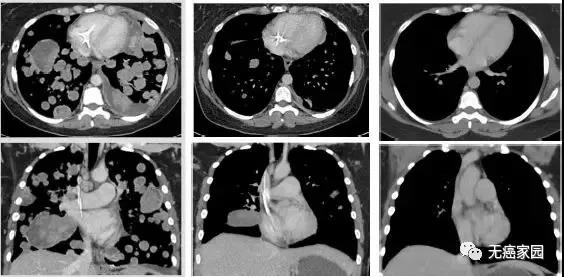

图示分别为治疗前、治疗3周期第1天、治疗13周期第1天

现在,她的随访扫描结果显示,在过去三年她都已经没有癌症的迹象!